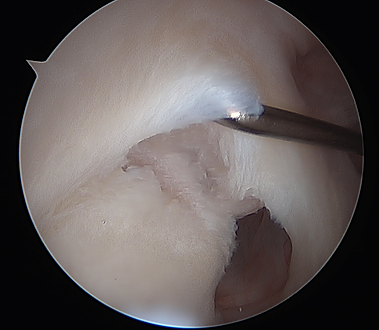

Anterior-inferior labral tear, or "Bankart Tear."

The labral tear after arthroscopic repair.